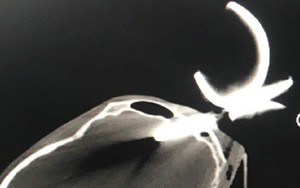

Cứu sống người đàn ông bị dị vật kim loại cắm vào hộp sọ

Ngày 19/6, thông tin từ Bệnh viện Nhân dân 115 Thành phố Hồ Chí Minh cho biết, đơn vị vừa thực hiện ca phẫu thuật khẩn cấp cho một người đàn ông bị dị vật là một phần của bông cửa sắt hàng rào cắm thẳng vào hộp sọ.